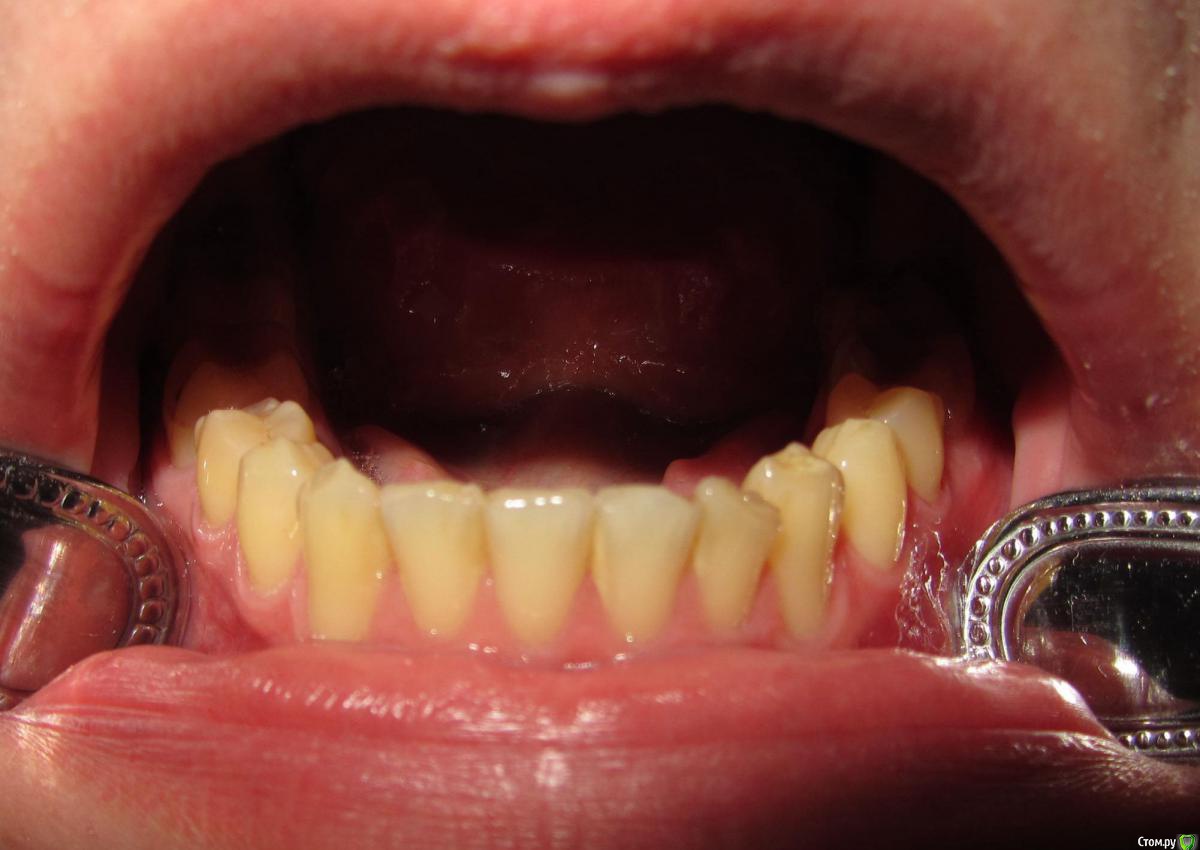

janis1 Опубликовано 14 ноября, 2015 Поделиться Опубликовано 14 ноября, 2015 Доброго времени суток, уважаемые профессионалы.Очень надеюсь на вашу помощь.Коротко о себе:37 лет, пол мужской. Так сложилось что в последнее время меня постигло сразу три проблемы,как мне кажется все они имеют между собой четкую связь. Основная проблема, с болями верхней челюсти, началась у меня около месяца назад. Боль не очень сильная, но практически постоянная. Боль не имеет какой-либо конкретной локации (болит именно вся челюсть). С утра она меньше, ближе к вечеру усиливается. В последнее время немного отдаёт в скулу. Одновременно с появлением боли, во рту, в районе дёсен, появился как бы привкус соды (немного похожий на вкус крови, но крови в ротовой полости нет).И в довершение всего начали катастрофически искривляются зубы верхней челюсти.На самом деле проблемы с прикусом у меня были уже с детства, примерно в 10 - 12 лет я носил пластинку для исправления прикуса.Но к сожалению лечение так и не закончил, соответственно прикус все это время у меня был неправильным, но до последнего времени он меня не беспокоил, так как был если так можно сказать "в пределах разумного", и в течении долгого времени был неизменен, но в последние несколько месяцев верхние зубы искривились настолько катастрофически что что я реально начал шепелявить. При попытке расшатывания зубы стоят крепко, не болтаются. Пока во всяком случае... Со всеми этими проблемами я пробовал обращаться к зубному хирургу и ортодонту,ни хирург, ни ортодонт к которым я обращался не смогли назвать каких-либо конкретных причин по которым может появляться боль в верхней челюсти и привкус во рту.Врачи к которям я обращался действительно хорошие специалисты, но похоже видят проблемы узко по своей специализации.Единственно хирург указал на то, что возможно придется удалять восьмерки, а ортодонт предложил установить брекеты на обе челюсти.Я прекрасно понимаю что с таким прикусом мне действительно не избежать установки брекетов, но меня беспокоит то, что не найдена причина происхождения всех проблем о которых я написал. Очень надеюсь на вашу помощь в поиске возможных причин проявления моих проблем. Заранее благодарен! Ссылка на комментарий

Jurai Опубликовано 22 ноября, 2015 Поделиться Опубликовано 22 ноября, 2015 Есть проблема во фронтальном участке верхней челюсти: общая убыль костной ткани, ячеистая структура кости. смещение зубов так, что корни изогнулись, это значит, что либо резорбция (рассасывание) либо очень длительное уже идет воздействие. Могу подозревать новооборазование в этом участке.Вам нужна консультация челюстно-лицевого хирурга-онколога. 1 Ссылка на комментарий